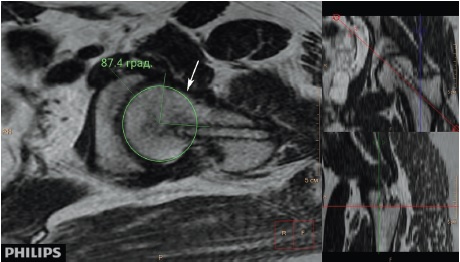

Рис. 4. МРТ левого тазобедренного сустава пациента 18 лет 7 мес. через 5 лет 2 мес. после операции, радиальный срез на уровне перехода «головка – шейка», перпендикулярный оси шейки бедренной кости, Т2-взвешенное изображение). Деформация перехода «головка – шейка» (обозначена стрелкой) — избыток костной массы в передневерхней части перехода, нарушающий сферичность головки бедренной кости